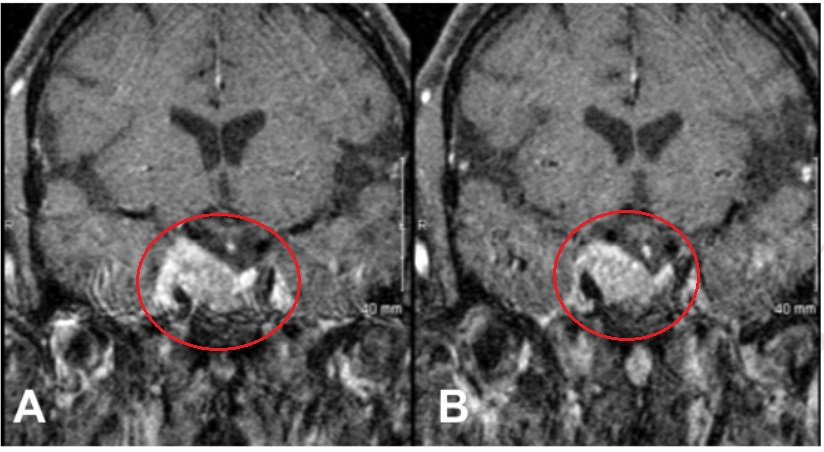

▼术前肿瘤持续生长进入海绵窦

完成放疗一年后,当她出现右侧动眼神经麻痹症状时,磁共振成像检查显示右侧鞍旁间隙内的肿瘤出现了进一步进展。医疗团队采用了标准的内镜经鼻经蝶入路,并通过移除覆盖在颈内动脉海绵窦前升段上方的骨质向侧方扩大手术通道。随后使用多普勒超声探测颈内动脉,并锐性切开其内侧和鞍区外侧的硬脑膜以进入内侧通道。松动的复发性软组织肿瘤被分离。颈内动脉海绵窦水平部被显露并从肿瘤组织中游离出来。确认海绵窦内侧壁似乎完整,与鞍区无明显沟通,而通过正常中线鞍区通道观察,鞍区内未见肿瘤。沿颈内动脉后下方可见第三对颅神经。